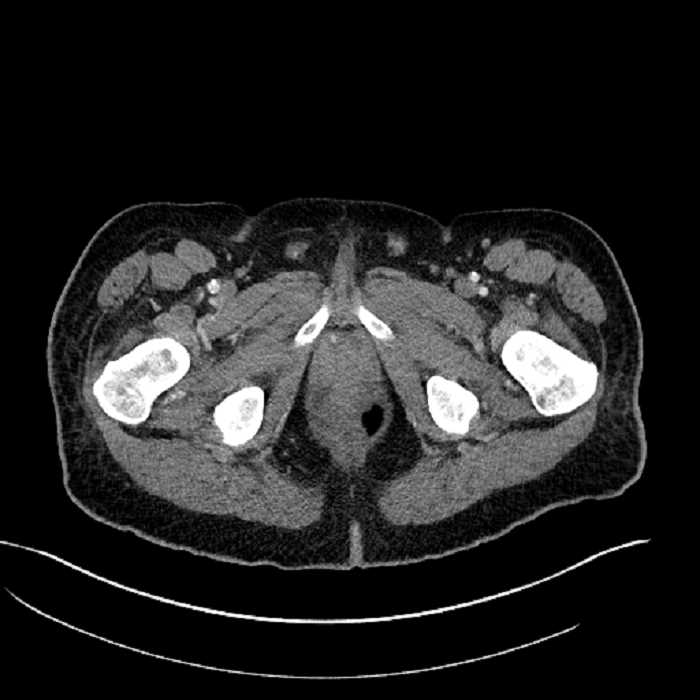

Age: 63

Sex: Male

Indication: Abdominal pain

• Mild mural thickening of a segment of the sigmoid colon with adjacent fat stranding and a 1.5 cm fluid and gas collection along the tip of an inflamed diverticulum

• Loss of the normal fat plane between this collection and adjacent loops of small bowel, which demonstrate mural thickening

• High grade stenosis of the left common iliac artery, with the left internal and external iliac arteries remaining patent

• Ankylosis of both sacroiliac joints

Acute sigmoid diverticulitis complicated by a small contained perforation and a large abscess in the right hepatic lobe. Additional small subcapsular abscesses along the anterior margin of the left hepatic lobe.

Additionally, loss of the normal fat plane between the peridiverticular collection and adjacent thickened loops of small bowel raises the potential for an enterocolonic fistula.

High grade stenosis of the left common iliac artery. The left external and internal iliac arteries are patent.

Hepatic abscess showing the double target sign with low density internally surrounded by a thin inner enhancing rim (red arrow) and ill-defined outer low density rim (yellow arrow). Blue arrow indicates an internal septation. Red arrows: additional smaller subcapsular abscesses. Red arrow: focal contained perforation associated with diverticulitis.